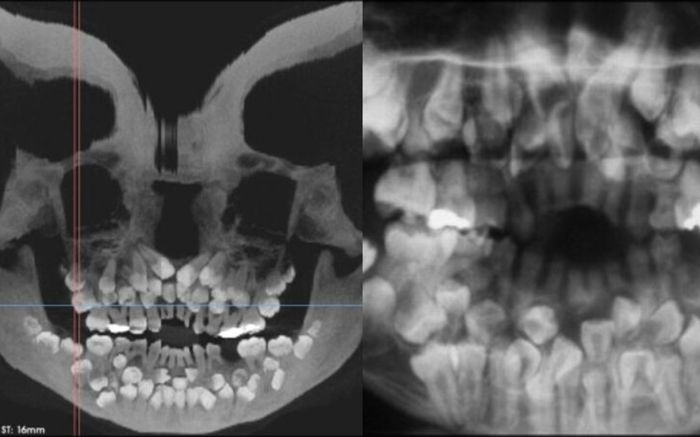

Bé gái 11 tuổi mọc 81 chiếc răng